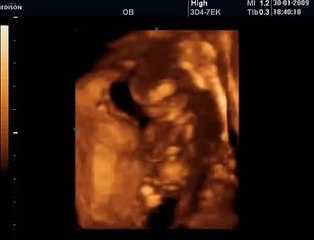

www.cemturan.combr www.dr-cemturan.combr www.jinekolojikonkoloji-istanbul.combr www.perinatoloji-istanbul.combr Hamilelikte renkli Doppler ultrason niçin yapılır? Bebek renkli mi görülür yoksa damarları görmek için mi renkli Doppler yapılır? Prof. Dr. Cem Turan'dan izleyin. Renklli doppler ultrason ile en çok incelenen damar bebeğin göbek kordonundaki damarlardır (umblikal damarlar). Bunun dışında rahim damarları, beyin damarları, kalp damarları gibi çeşitli damarlar incelenebilir. Özellikle rahim içerisinde gelişme geriliği (iugr) şüphesi olan bebeklerde, anomali varlığında, kalp ritm bozukluğu veya kardiyak anomali varlığında, yüksek tansiyon hastalarında yapılır. Her gebelikte rutin olarak yapılan bir inceleme değildir.